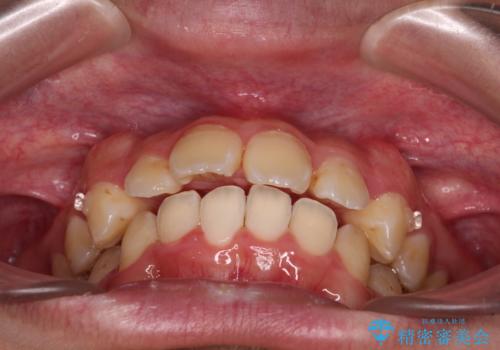

- 深く咬みこんだ前歯と、それに伴い前方に突出した上顎前歯を気にして来院された患者様です。

下顎の歯列は、奥歯が前方に傾斜し、前歯が上顎の歯の付け根に食い込むように内側に傾斜していました。

また、左右の犬歯の位置関係は上顎歯列が前方に位置する咬み合わせとなっており、インビザライン単体で治療するよりは、ワイヤー装置や補助装置を併用した方がより良い仕上がりになることが期待されました。